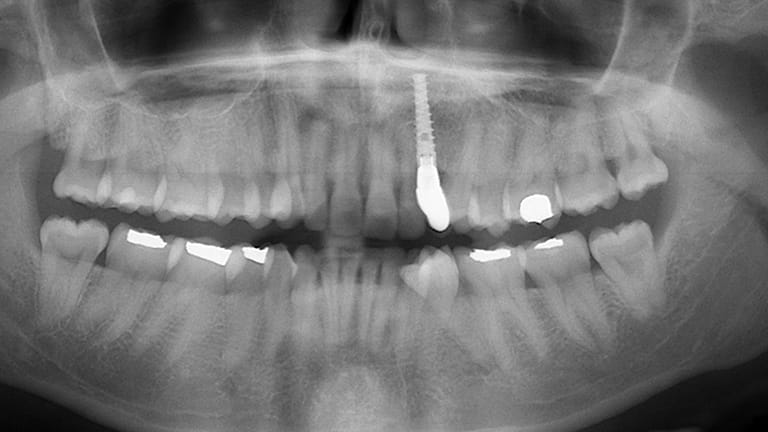

Dental implants are a titanium "root" which can be placed into the jawbone. Once integrated with your bone, the implant can be used to support a crown, a bridge, or secure a complete denture. Dental implants may be used to eliminate partial plates and dentures. The success rates for dental implants are extremely high which is due in part to the fact that root-form implants are made of a biocompatible material, titanium.

Single Tooth Replacement

Below is a few examples of what DENTAL IMPLANTS can do for you and your smile!